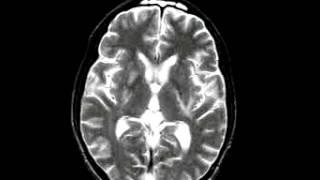

Cerebrovascular Disease Multiple embolic infarction, diffusion and FLAIR imaging

DR. DONG-KYUN KIM

Dr Dong Kyun Kim. Смотреть видео: Degenerative Disease Alzheimers Dementia, Metastatic Carcinoma Of The Colon Spatial, Cerebrovascular Disease Fatal Stroke, Neoplastic Disease Metastatic Adenocarcinoma.